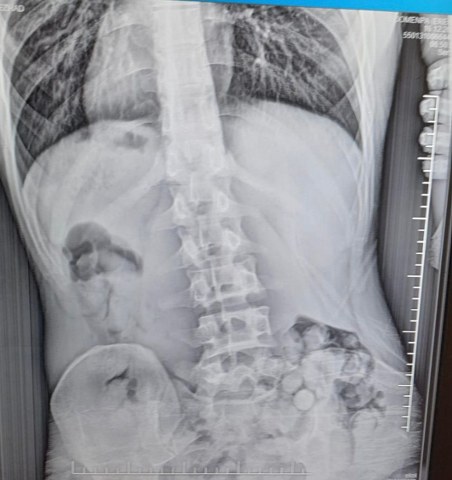

Narkotik Suçlarla Mücadele Şube Müdürlüğü ekipleri, uyuşturucuyla mücadele kapsamında Çarşamba ilçesinde bir operasyon düzenledi. Operasyonda, yabancı uyruklu R.B. (21) isimli şahıs şüphe üzerine gözaltına alındı. Yapılan iç beden muayenesi sonucunda, 51 kapsül halinde toplam 309 gram metamfetamin ele geçirildi.